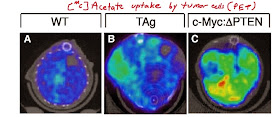

PET image analysis confirmed that tumors could efficiently incorporate acetate.